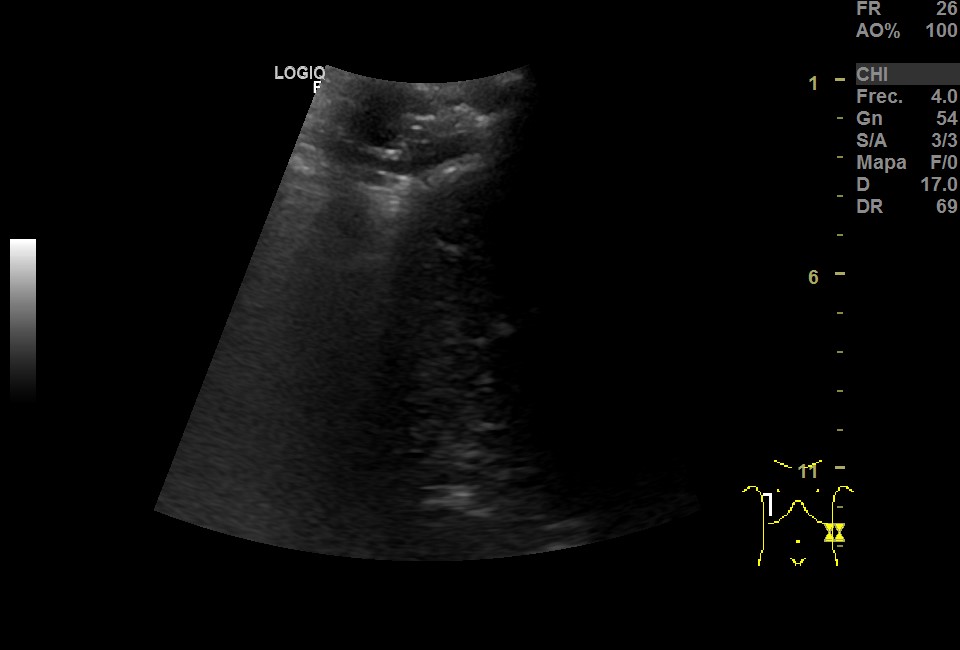

Ecografía pulmonar: imagen hipoecoica irregular subpleural, con signo de desflecamiento, limitada superiormente por la línea pleural e inferiormente por una línea irregular en sacabocados donde aparece un punteado hiperecoico sobre múltiples líneas B que muestran imagen de pulmón blanco. Todo ello sugestivo de consolidación pulmonar con broncograma aéreo. Imagen de medusa sugestiva de pequeño derrame pleural.